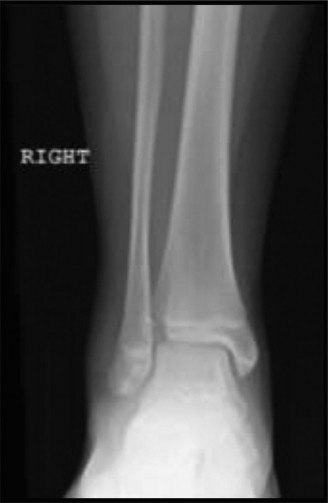

CASE 8 A 7-year-old girl is transferred to the ER after suffering an injury pl…